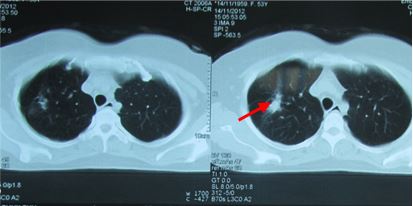

- So sánh trên hình ảnh CT u phổi di căn não trước và sau điều trị (ĐT)

Hình 6: U phổi trước ĐT

Hình 7: U phổi sau ĐT 16 tháng, tổn thương xơ hóa nhỏ